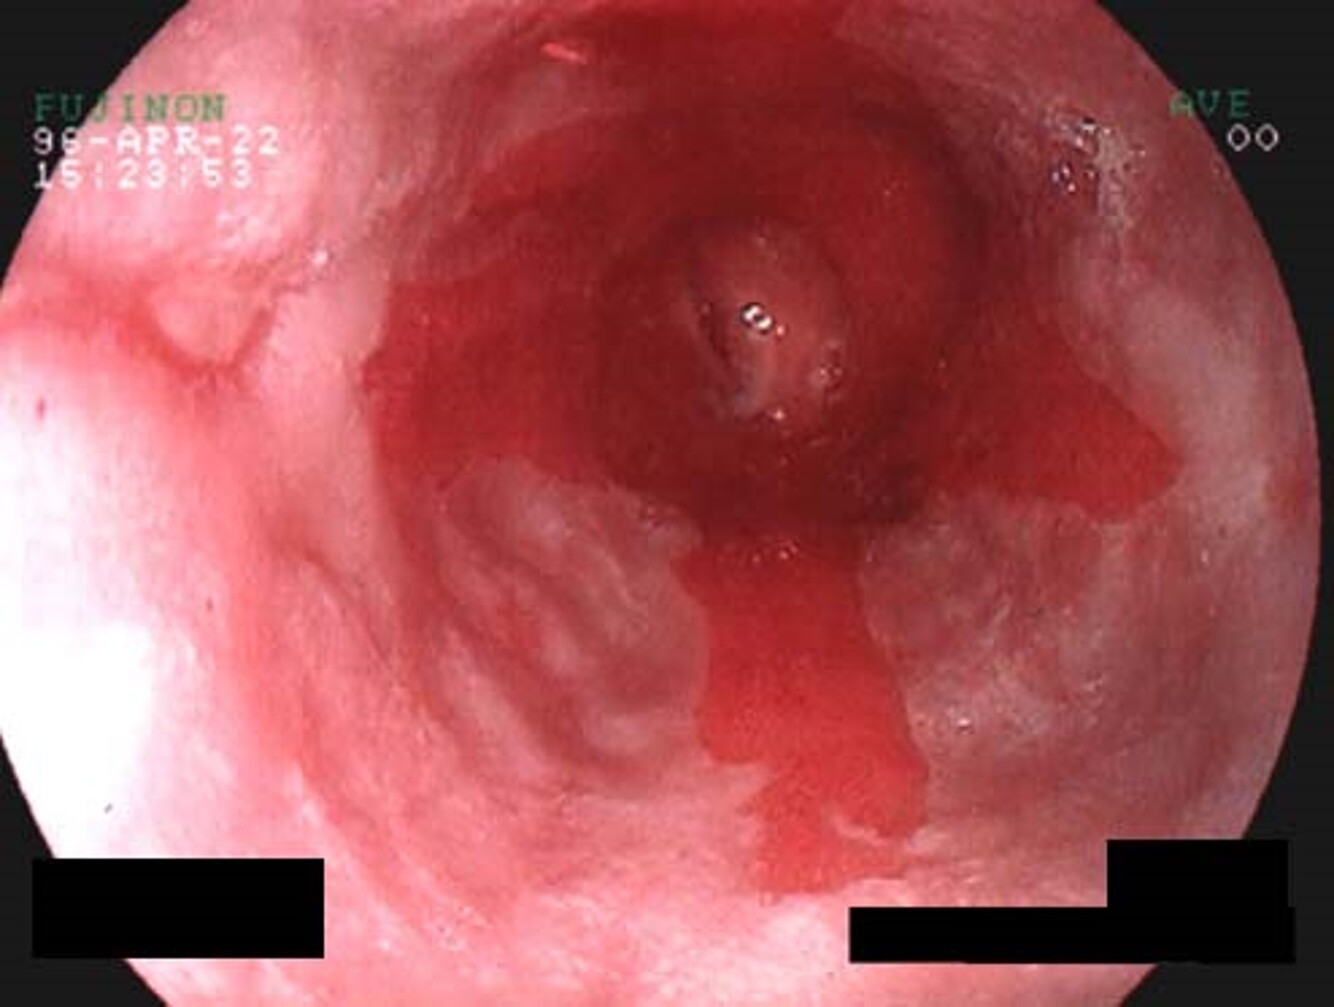

What pathology is seen here?

Esophageal Varices

Esophageal Varices (severe)